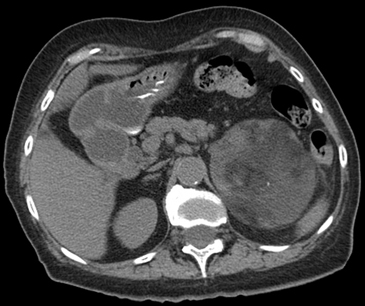

En la TC no contrastada las glándulas suprarrenales normales son homogéneas y simétricas, con una densidad muy similar a la del parénquima renal adyacente (Figura 1 a). Con un medio de contraste ev la glándula suprarrenal se opacifica en forma homogénea, similar al hígado o al bazo (Figura 1 b). Si la cantidad de tejido adiposo retroperitoneal es abundante las glándulas suprarrenales pueden aparecer enteramente rodeadas por grasa y su delimitación es más fácil (Figura 2 a); lo inverso ocurre en pacientes muy delgados con escasa grasa retroperitoneal (Figura 2 b). En RM, en secuencias ponderadas en T1 y T2 convencionales tienen una intensidad de señal homogénea, hipointensa respecto de la grasa adyacente e iso o hipointensa con respecto del parénquima hepático (Figura 3 a y b). En los cortes coronales se aprecia mejor la forma y la posición de las glándulas suprarrenales (Figura 3 c).

Figura 1. Glándula suprarrenal normal en tomografía computada. Cortes axiales de tomografía computada, donde se identifica la morfología normal de la glándula suprarrenal derecha (flecha) en fase no contrastada (a), y tras el uso de medio de contraste endovenoso (b).